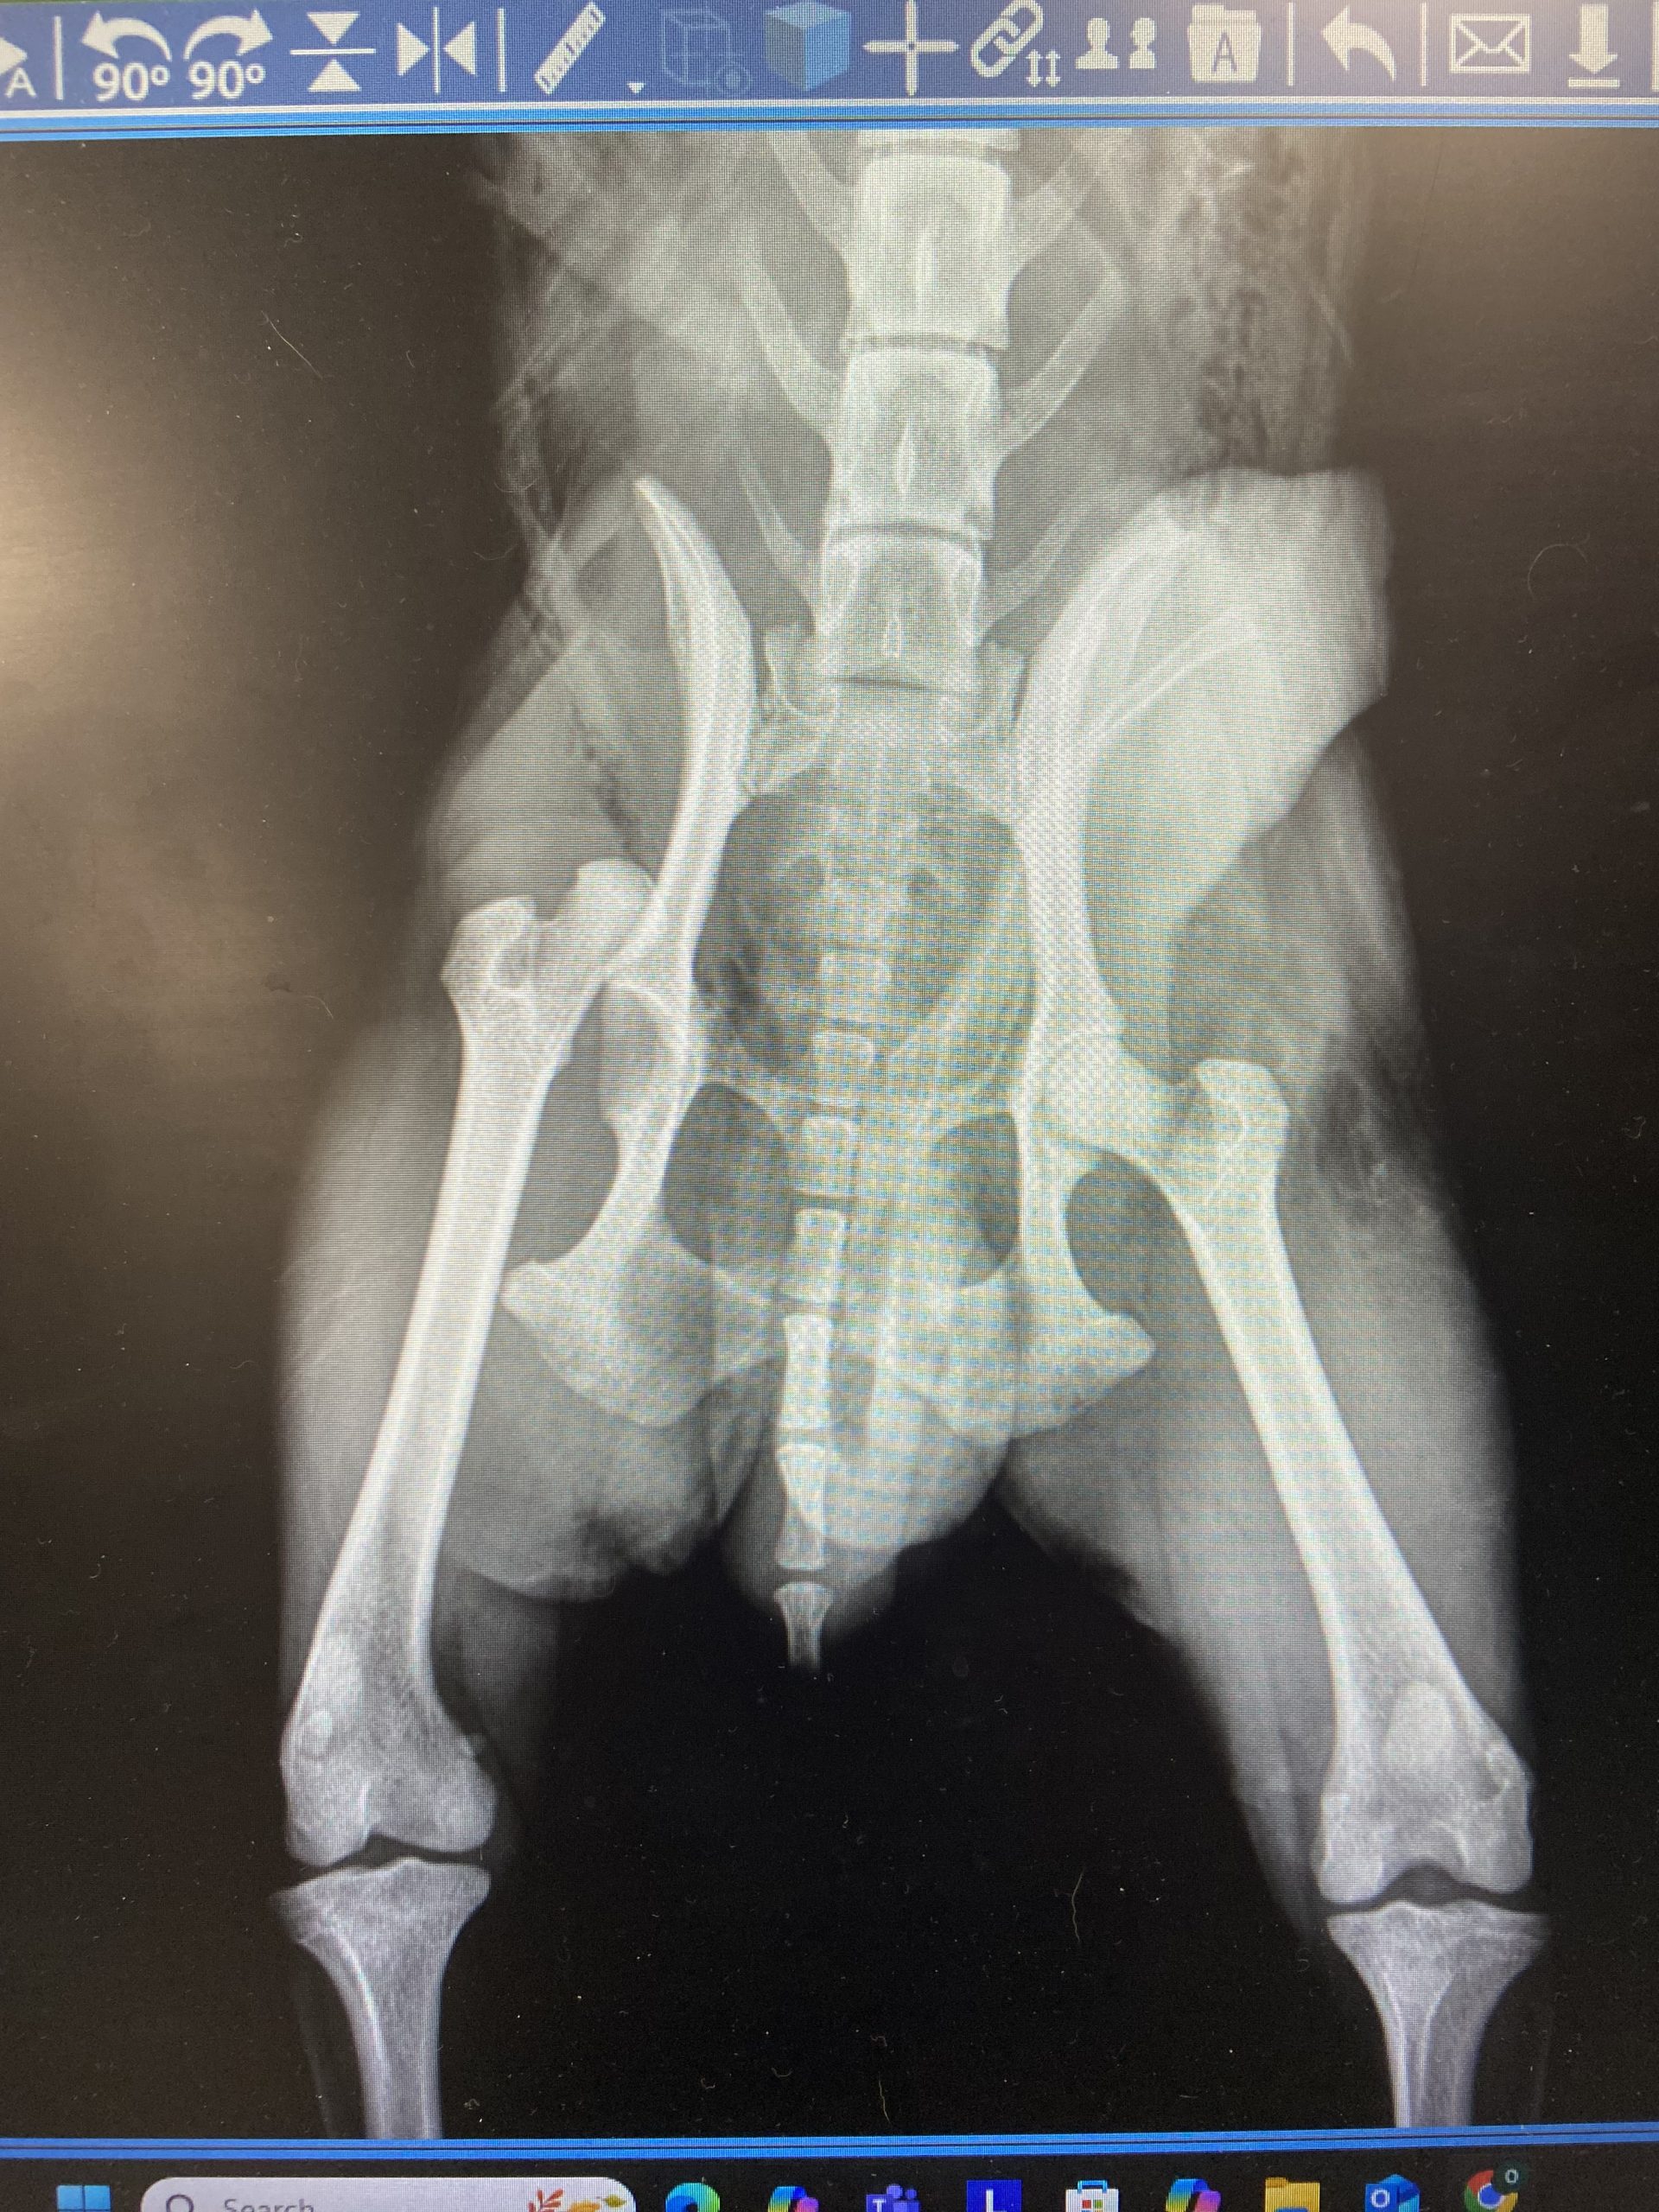

Draco may be just 7 pounds, but his spirit is larger than life! This adorable Pomeranian is a true testament to resilience, joy, and the power of love. After overcoming a serious injury, Draco has healed beautifully and is now thriving, happy, confident, and ready to find his forever family.

Thanks to the incredible care of our veterinary team, Draco made a full recovery and hasn’t let his past slow him down one bit. Today, he’s a cheerful, fluffy little guy who loves life and embraces each day with enthusiasm.